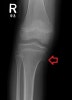

X-ray : Pes anserius spur

간혹 점액낭 주위에 뼈가 툭 튀어나온 사람도 있습니다. 생각보다 흔한 소견이며 그렇게 뼈가 튀어 나와 있어도 통증이 없는 사람도 많습니다(증상이 없다면 치료의 대상이 아닙니다).